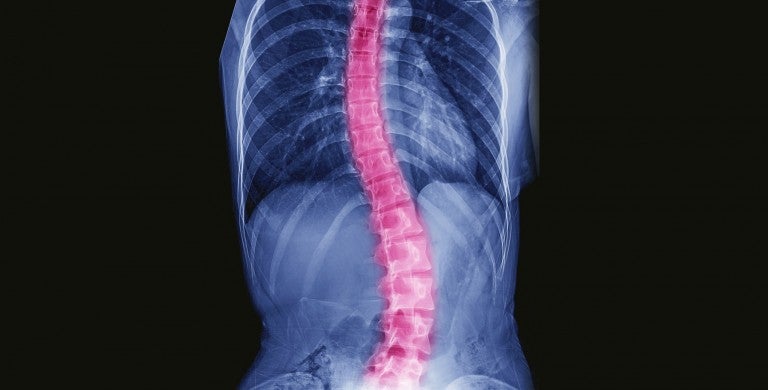

Scoliosis is a curve in the spine that causes the spine to look like an “S” or a “C.” Doctors measure the spine to determine if a person has scoliosis. A curvature of 10 degrees or more is considered scoliosis.

• X-ray: An X-ray provides detailed pictures of internal tissues, bones and organs.